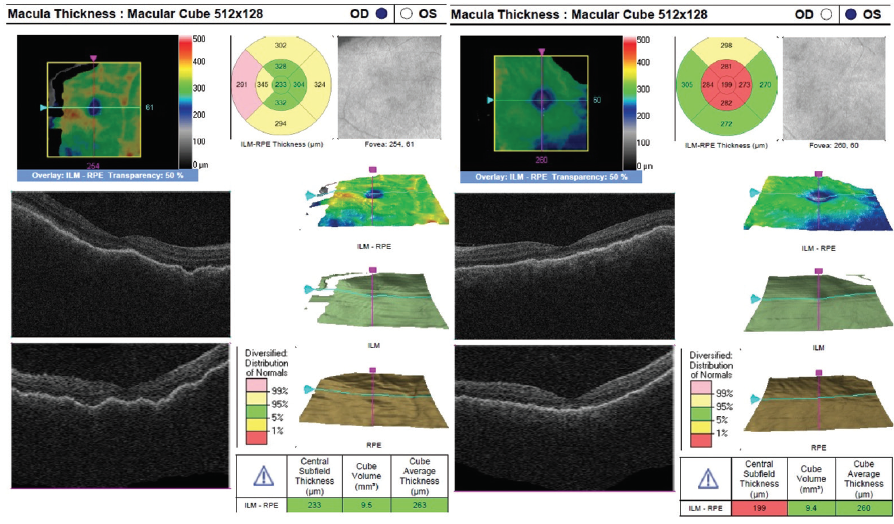

The patient showed a robust initial response to steroids with significant improvement in her vision and anatomy. Within 1 week, her VA had improved to 20/100 OD and 20/70 OS. Fundus examination showed improvement with less defined lesions (Figure 4), and OCT showed significant reduction in fluid (Figure 5). After 1 month of treatment, her vision had improved to 20/50 OD and 20/40 OS, with further improvement seen on fundus findings (Figure 6) and near complete resolution of fluid on OCT (Figure 7). Continued improvement was seen 6 weeks after steroid therapy was initiated (Figure 8 and Figure 9). The marked improvement in structure and function with oral prednisone treatment, without ATT treatment, led to a presumed diagnosis of VKH disease.

Figure 7. OCT at 4 weeks of oral prednisone steroids show near resolution of retinal fluid OU.

Figure 9. OCT at 6 weeks of oral prednisone show complete resolution of retinal fluid OU.